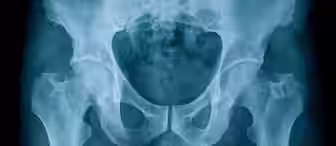

I have developed a sub-speciality representing the families of babies with late diagnosis of hip dysplasia and am currently running more than 20 such cases. Because of this, I work closely with the Charity STEPS, providing training for their helpline staff and talking to beneficiaries who want to consider bringing a claim.

Watch our videos answering frequently asked questions about claims involving hip dysplasia.